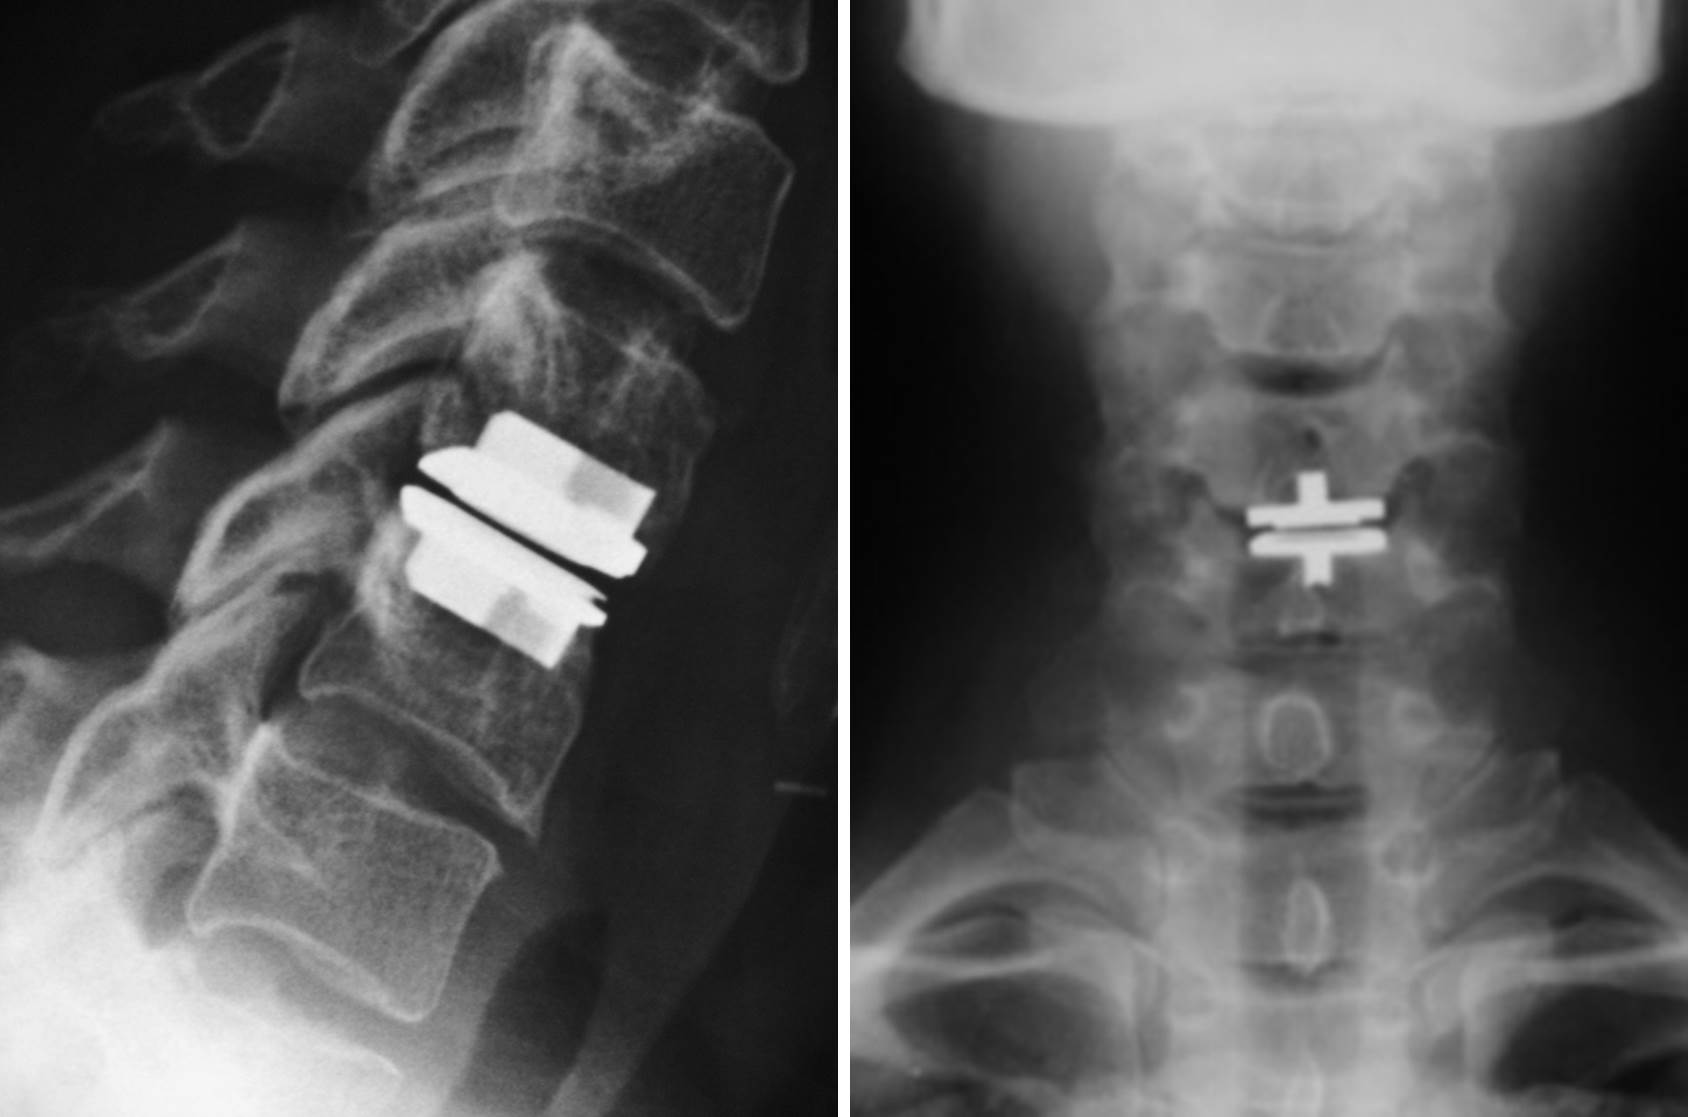

From radiopaedia.org

Cervical disc replacement Image Reviews Of Cervical Disc Replacement Acdf and disc replacement surgery can both take your neck pain and radiculopathy away. Which one’s right for you? Like a knee replacement surgery, the artificial disk allows for full or nearly full range of motion after the surgery. Learn about how they’re similar and different to. Let’s explore the pros of cervical disc replacement surgery in detail: One of. Reviews Of Cervical Disc Replacement.